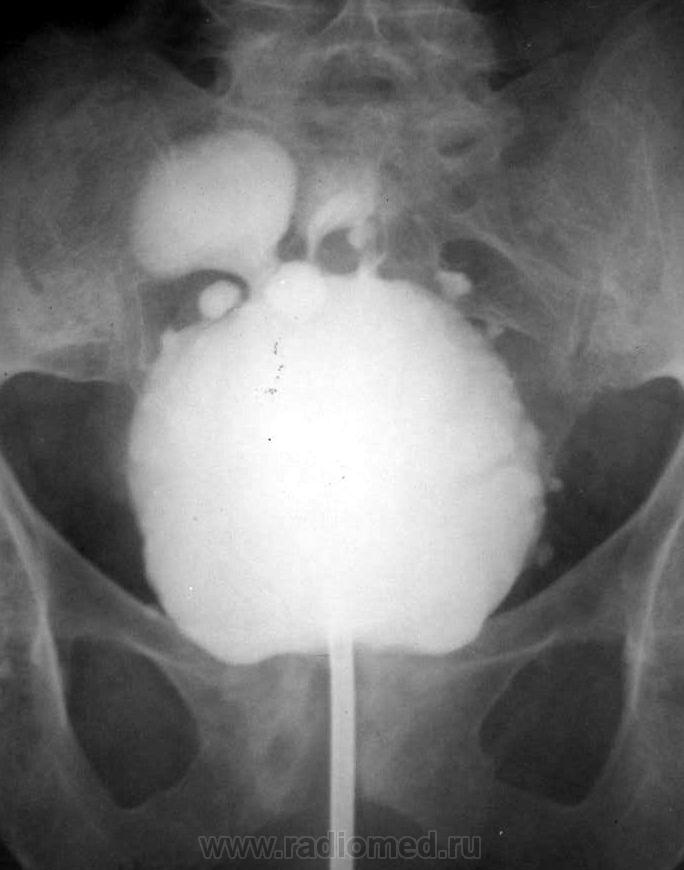

Архив. Выраженный хронический цистит. Цистография.

Из архива кафедры. Нечасто встретишь такое. Цистография. Фаза тугого заполнения и после микции.

Видел от силы 3, но чтобы такую "махровость" - никогда. Интересно, чем объяснить заброс контраста в дистальные отделы мочеточников после опорожнения?

Видимо, недостаточность клапанной функции устья из-за рестриктивных изменений.

А это не множественные дивертикулы?